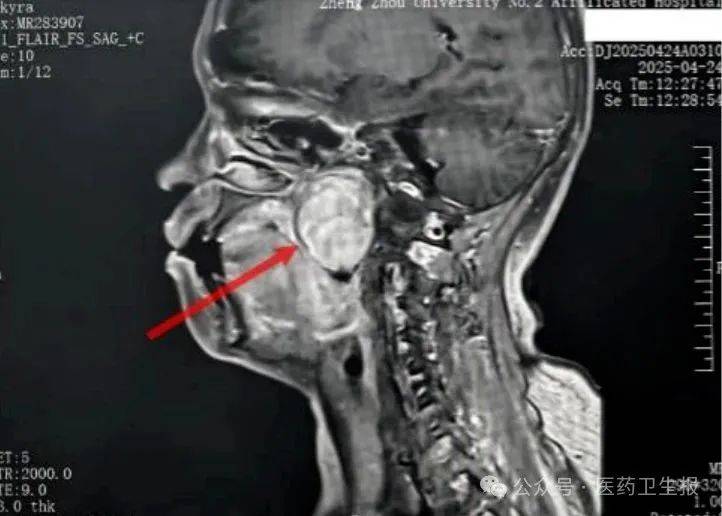

患者张某因右侧面部感觉异常、吞咽食物时咽部异物感到当地医院就诊,被查出咽部右侧深部间隙内存在直径6厘米~7厘米的巨大肿瘤。

由于该区域解剖结构复杂,张某初诊时被误诊为鼻咽癌。因治疗效果不佳,张某被转诊至郑州大学第二附属医院。耳鼻咽喉科主任医师米彦芳经过系统检查,考虑良性肿瘤可能性大,但因瘤体巨大,涉及颅底、面神经、颈内动脉等重要结构,遂请神经外科、医学影像科医生进行会诊。术前,他们通过三维重建,精准规划手术路径。最后,神经外科主任医师陶胜忠和米彦芳决定实施经口入路右侧咽旁间隙肿瘤切除术。